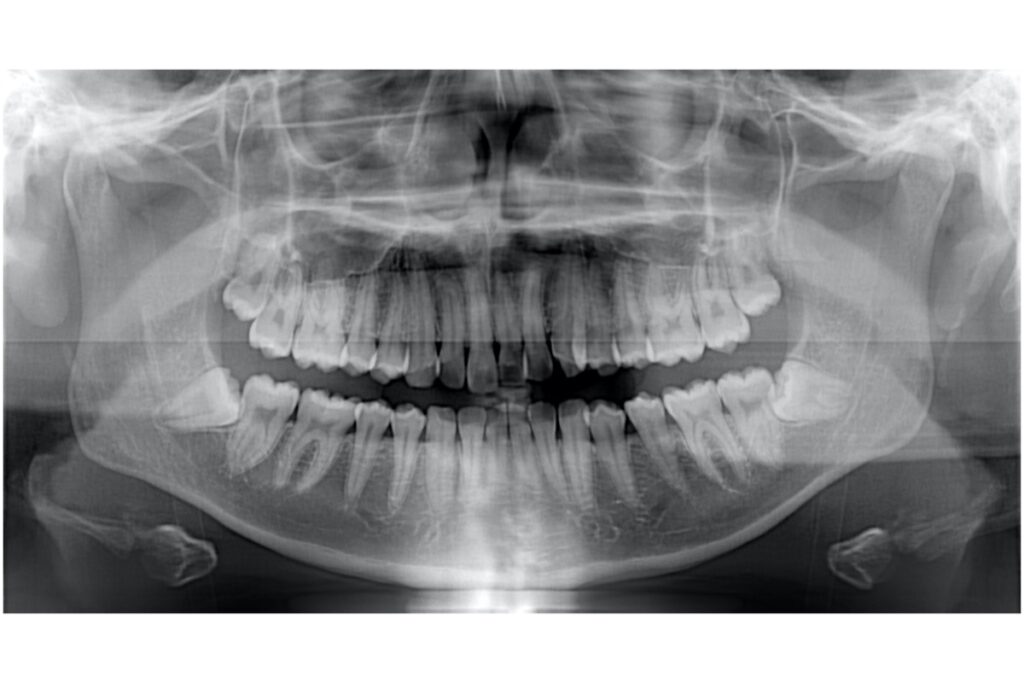

- レントゲン撮影(セファロ・パノラマなど)